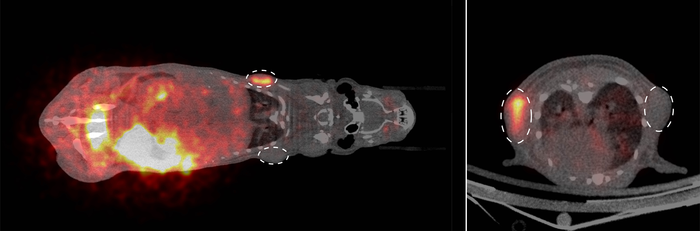

PET imaging of tumours (dashed circles) in a mouse (right in cross-section) using SNAP-tag technology

image: PET imaging of tumours (dashed circles) in the body of a mouse (right in cross-section). Researchers used a newly developed radioactive substrate to label tumour cells in a living organism. Cells genetically modified to produce a so-called SNAP-tag enzyme took up the radioactive marker (orange), while cells without this enzyme did not. view more

In microscopy, fluorescent dyes are used to label cells, but they are mostly not suitable for whole-body imaging because their signals are scattered by thicker tissue layers with the result that they can no longer be measured. To solve this problem, the scientists synthesised a new SNAP-tag substrate using the radioactive signal emitter fluorine-18. The team have successfully labelled tumour cells in mice by injecting this substrate into the organism via the bloodstream and were then able to visualise the tumours using PET imaging. “The exciting thing for us about SNAP-tag technology is that it opens up the prospect of visualizing genetically encoded cells in the body with different imaging modalities and at different temporal stages – we call it multiscale imaging,” explains nuclear medicine specialist Prof Michael Schäfers. “Radioactive signals from fluorine-18 remain stable for only a short time,” adds radiochemist Dr Christian Paul Konken, “but as we can repeat the second labelling step, we can potentially visualise the same cells again and again over days and weeks.” The high level of detail provided by microscopy makes it possible to study how individual cells communicate with each other. The big picture view provided by whole-body imaging enables scientists to assess how these cells function as part of whole organ systems. Time may reveal what role individual cell types play in inflammation, for example, as it begins, continues and resolves. “Only by combining all this information can we understand how everything is connected in the body,” says Michael Schäfers.

The scientists first checked whether the synthesised substrate remained stable when in contact with blood in the test tube and then examined how the cells interacted with the substrate in the first practical tests in cell cultures. In doing so, they compared human tumour cells into which they had genetically incorporated the SNAP-tag enzyme with those that did not produce the enzyme. “We could see very clearly that the radioactivity was only taken up by the cells that produced the SNAP-tag enzyme,” says Dominic Depke. Finally, the team conducted targeted studies on individual mice. “This step was decisive once again,” explains Michael Schäfers, “because how a molecule behaves in the complex biological environment in a living organism cannot be fully simulated in cell culture or with artificially produced organs.” The scientists were able to show that once the substrate is injected into the bloodstream it is distributed through the body very quickly. Additionally, they identified the pathways through which it is excreted. They then compared how tumour cells with and without the SNAP-tag enzyme reacted to the substrate in living organisms. For this purpose, the tumour cells were injected under the skin of mice and removed again after the examination in order to confirm the results with autoradiography.